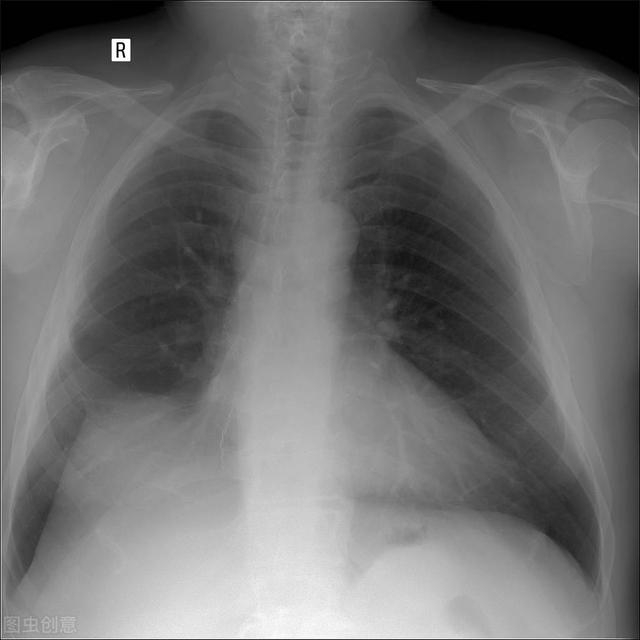

为了进一步深入了解我专门调取了他之前肺结节的片子,发现这个肺结节在右肺下叶的地方,虽然生长非常缓慢,但确实在发生变化。

如今,老人的这个肺结节长在右肺的下叶和中叶交界的地方。它侵犯了中叶,长在中叶的部位,发生跨叶生长,所以必须按照联合中下叶的切除才能切干净。

检查肺癌最常用、最标准的手段目前还是胸部CT检查,因为CT分辨率高,比其他的胸片等检查,看得更清楚。因此能发现很多小于1公分的,几毫米的,密度非常淡的早期病灶。